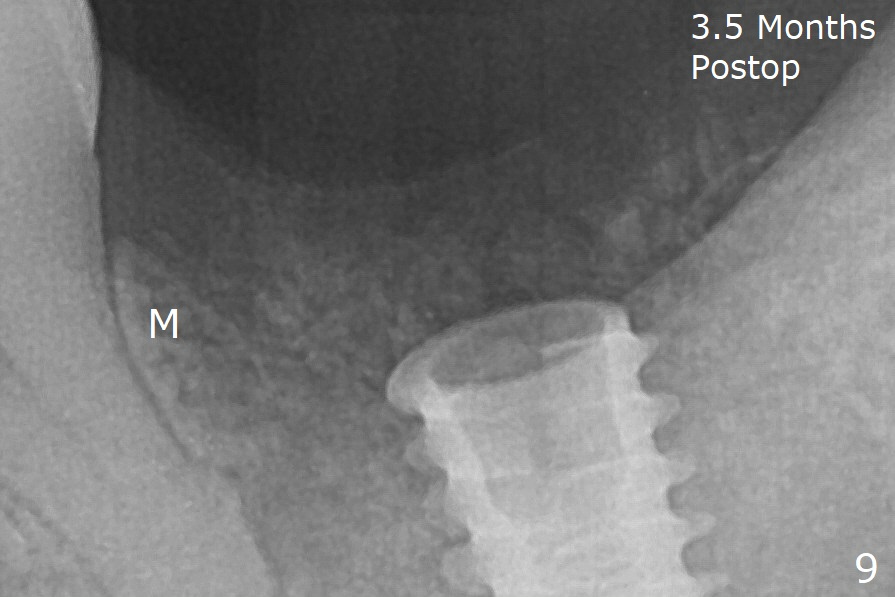

In fact the mesial crest is resorbed 3.5 months postop (Fig.9 M, as compared to that of preop and immediate postop in Fig.0,1). Continuous resorption may be associated with food impaction when a permanent crown is delivered. The preventive remedy would be socket shield, mesial and distal (Fig.0' M, D).